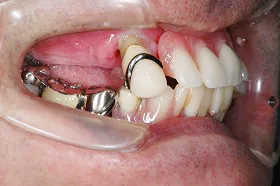

上下に入れ歯を入れていましたが、ここ数年しっかりと噛む事がなかった患者様です。何でもおいしく食事ができるようになりたいと希望され、来院されました。

治療法としては、最小限のインプラントの本数で対応ができるように、オールオンフォーを意識した治療法で対応させて頂きました。

| 主訴 | 噛めない |

| 治療方法 | 上顎8本、下顎6本のインプラントを埋入し固定性の入れ歯で治療した |

| 治療期間 | 約1年 |

| 通院回数等 | 20回 |

| 費用 | 上顎4,130,000円 下顎3,630,000円(税込) |

| リスク・副作用 | 治療後に一時的に腫れることがある |